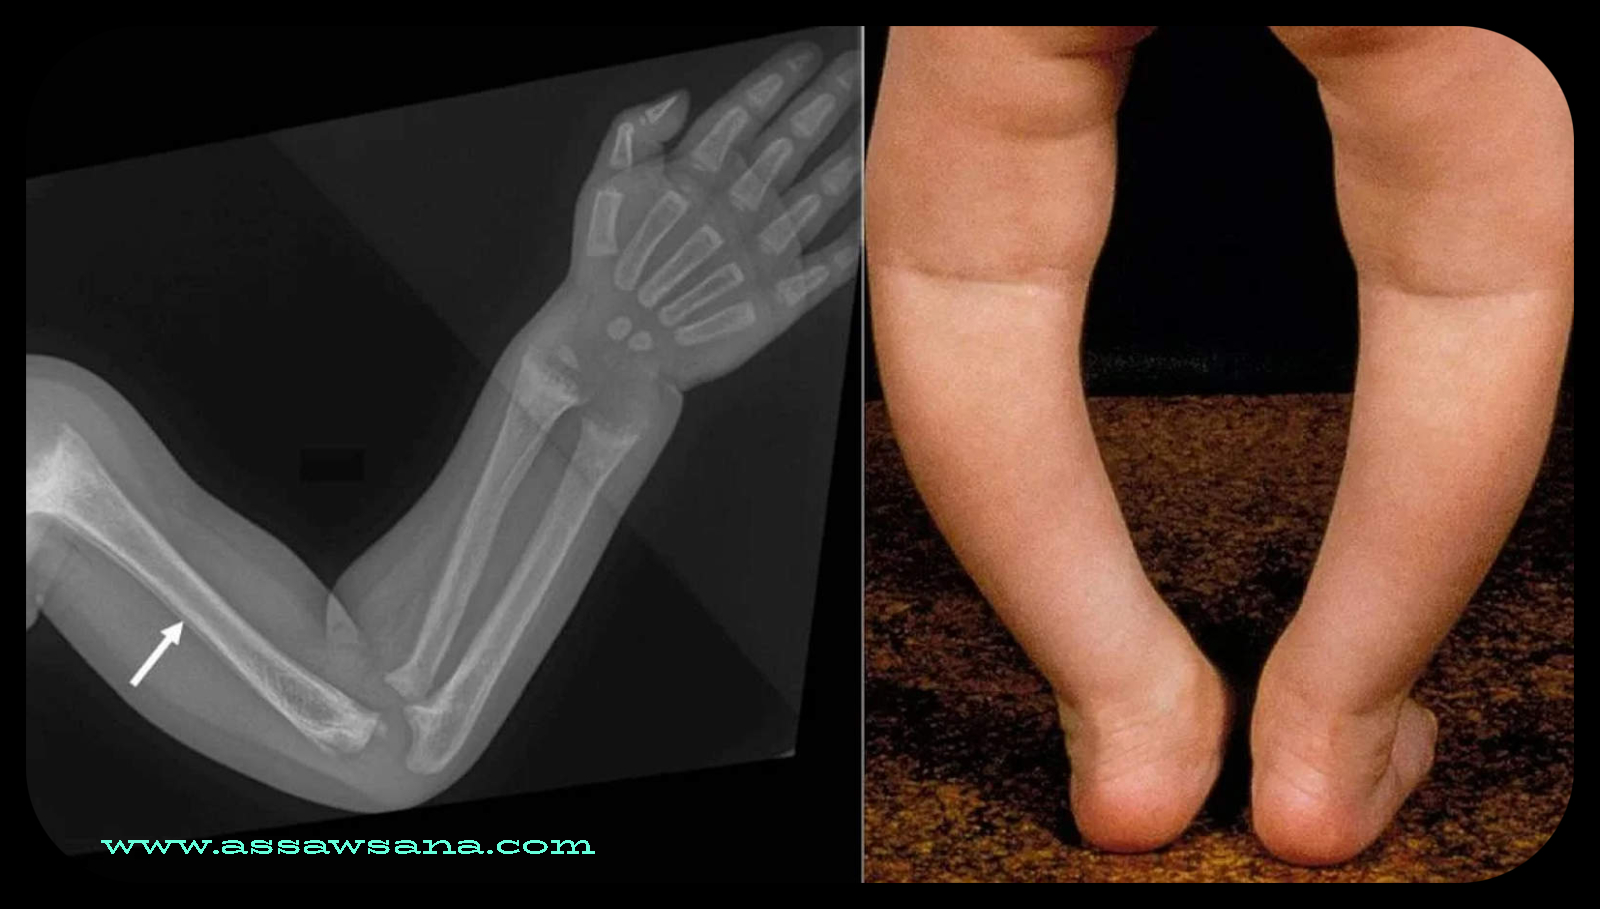

هناك أعراض متعددة تظهر على الطفل المصاب بلين العظام، تجعل الأهل يلاحظون إصابته بهذا المرض، ومنها: (تأخر في نمو الطفل، أو تأخر في ظهور الأسنان، وقصر القامة، وحدوث كسور متكررة للطفل، وشكل الساقين يكون غير طبيعي ومنحني).

يجب التأكد من إصابة الطفل بمرض لين العظام بعد ملاحظة عدم نموه بشكل سليم، وذلك بالذهاب إلى طبيب الأطفال المختص بذلك، وتشخيص حالته من خلال الأشعة السينية للعظام، أو بعض الفحوصات المخبرية، وبعد التأكد من إصابة الطفل بمرض لين العظام، فإنه يجب البدء بالعلاج بأسرع وقت؛ كي يشفي الطفل، وتنمو عظامه بشكل سليم.